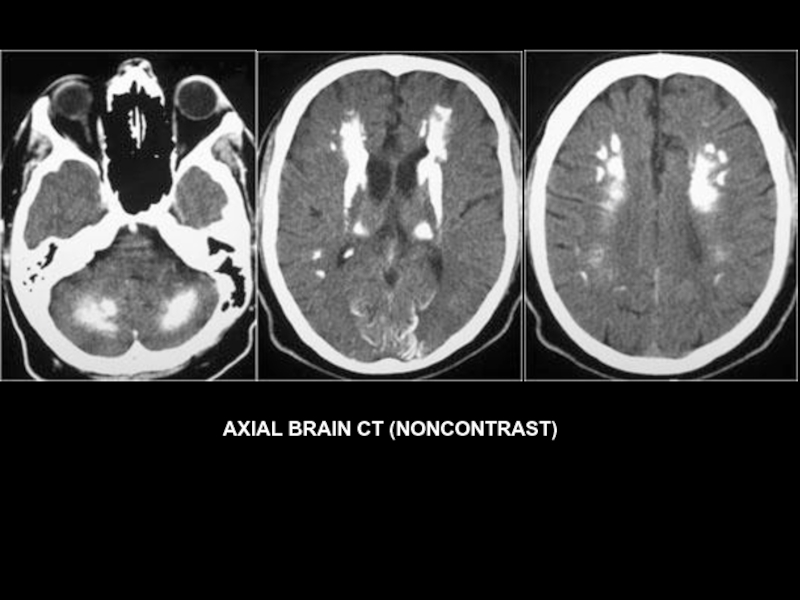

AXIAL BRAIN CT (NONCONTRAST)

Слайд 38

Слайд 39

Слайд 40

Слайд 41

Слайд 42